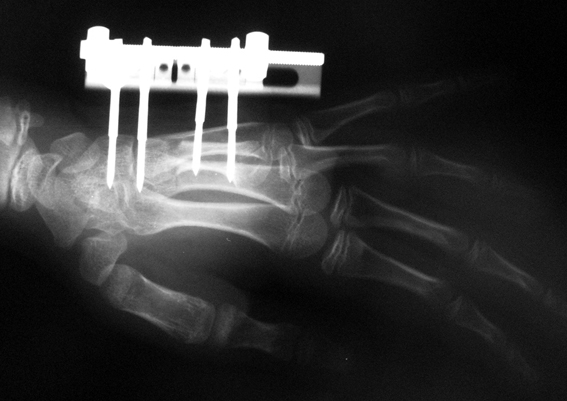

Surgical treatment may be required for metacarpal shortness because of cosmetic disturbance and fatigue in the dominant hand; and for metatarsal shortness because of cosmetic appearance, metatarsalgia, deformity due to dorsal shift of the short finger, pain and pressure ulcers due to plantar shift of the short finger, or difficulty in shoe wearing. Various techniques have been defined for the treatment of congenital metacarpal or metatarsal shortness. However, the most frequently used methods are acute lengthening with grafting, and distraction osteogenesis (callotasis). Callotasis method is preferred for lengthening more than 1 cm. In our department, we prefer distraction osteogenesis with unilateral or circular external fixator for lengthening of metacarpal and metatarsal bones.